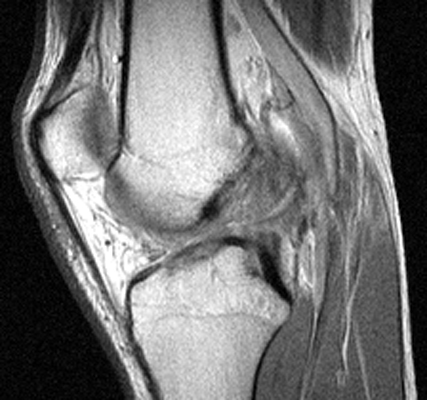

Sagittal T2 weighted and proton density images which reveal complete tear of the ACL with mild increase in marrow signal in the adjacent osseous structures. The bone bruises, as evidenced by increased signal within the marrow, is likely caused by anterior subluxation of the tibia at the time of tear of the ACL accompanied by impaction of the middle portion of the lateral femoral condyle against the posterior portion of the lateral tibial plateau. Signal intensity abnormalities are probably secondary to edema, hemorrhage, and microfracture.

T2W - Click on the image for a larger versionAProton Density - Click on the image for a larger versionB